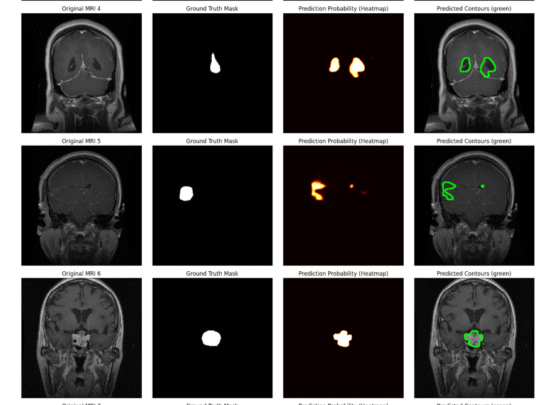

I provide advanced Computer Vision solutions for complex image and video-based projects.This service is ideal for businesses, research, and academic projects that require accurate and well-optimized...